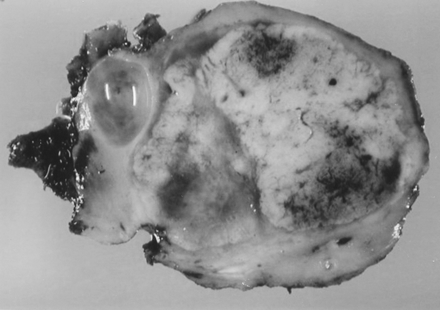

Nefroangioscleroza maligna (NSAM)

Nefroangioscleroza maligna (NSAM)           Definitie           Hipertensiunea arteriala maligna (HTAM) sau NASM se caracterizeaza printr-o hipertensiune arteriala severa   cu valori peste 230/130 mmHg, cu fenomene neurologice  severe (e